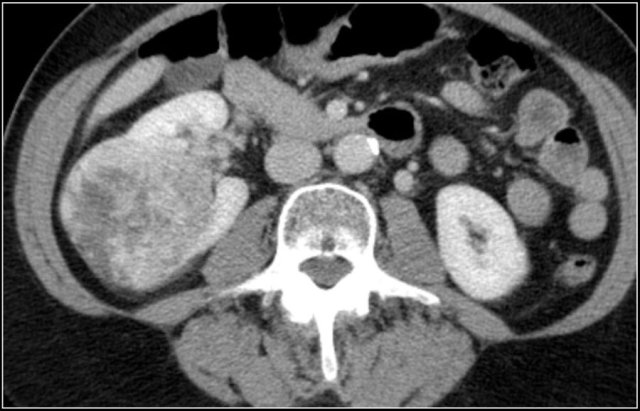

Multiple Angiomyolipomas

Sporadic AML is typically small, unilateral and asymptomatic, usually seen as an incidental finding.

In 10-20% of cases angiomyolipomas are multiple and bilateral.

This is mainly seen in patients with tuberous sclerosis.

Bleeding in Angiomyopiloma

Due to the abnormal vessels within an AML, it is prone to bleeding.

Patients can present with acute flank pain due to spontaneous hemorrhage.

The risk of hemorrhage increases with size.

Embolization was performed to stop the bleeding.

Preventive embolization is recommended in tumors larger than 4 cm, even in asymptomatic patients.

Notice the large vessels in the AML in the left kidney.